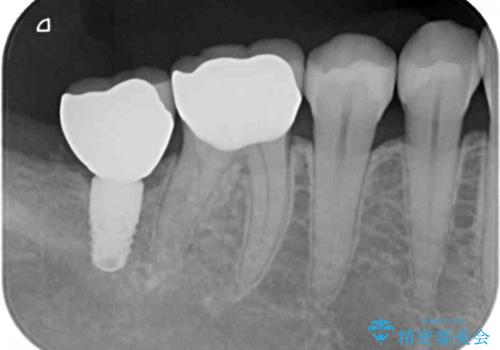

下顎の目立つ位置であるため、セラミックインレーによる修復治療を行うこととしました。

精密に型取りを行ったセラミックインレーを装着したことで、治療後にはしみたり痛んだりという症状は治まりました。